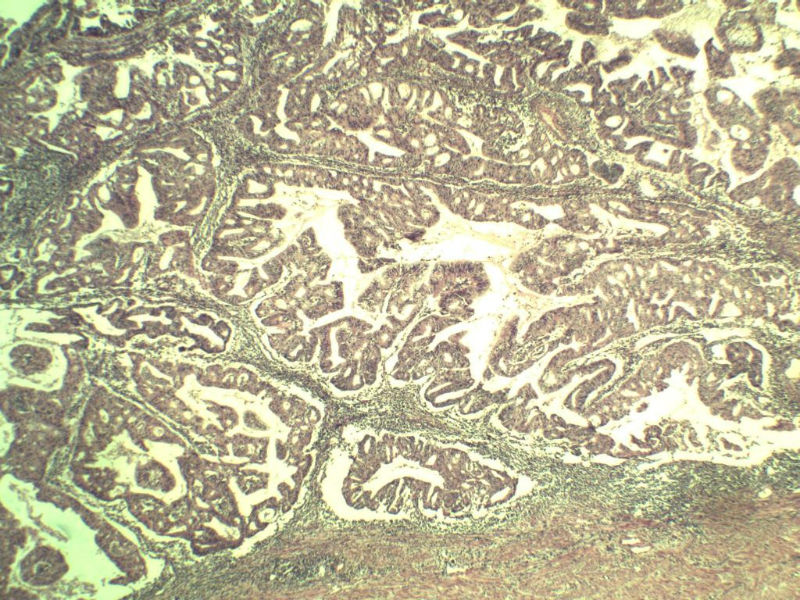

女,57岁,全切子宫一个,宫体体积 9 × 8 × 7 cm3,肌壁厚 2.5 cm,内膜菲薄,部分区域增厚达 0.4 cm(约3*2.5cm区域)。 请问各位老师  这个可以诊断子宫内膜癌了吧?      深肌层没有看到浸润。

患者因"发现下腹部包块1月多"入院  宫体体积 9 × 8 × 7 cm3,肌壁厚 2.5 cm,内膜菲薄,部分区域厚 0.4 cm(约3*2.5cm)。宫颈结构不清,长约 2.5 cm,表面欠光滑。临床诊断宫颈宫腔积液.

宫颈宫腔积液 内膜癌?图1

名称:图1

描述:a144.Jpg.jpg

宫内膜样腺癌

筛状、迷路样结构

间质消失或者纤维性间质

子宫内膜样腺癌

高分化子宫内膜样癌。浸润浅肌层(深度<1/3肌层)。根据FIGO2009分期,子宫内膜癌局限于内膜层和<1/2肌层,都属于IA期。二者处理不再区别对待。